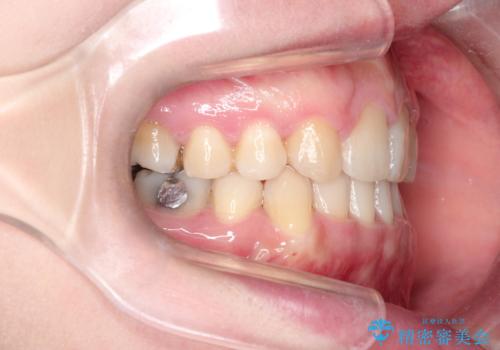

犬歯も通常の位置にまで移動することができ、口元もすっきりすることができました。